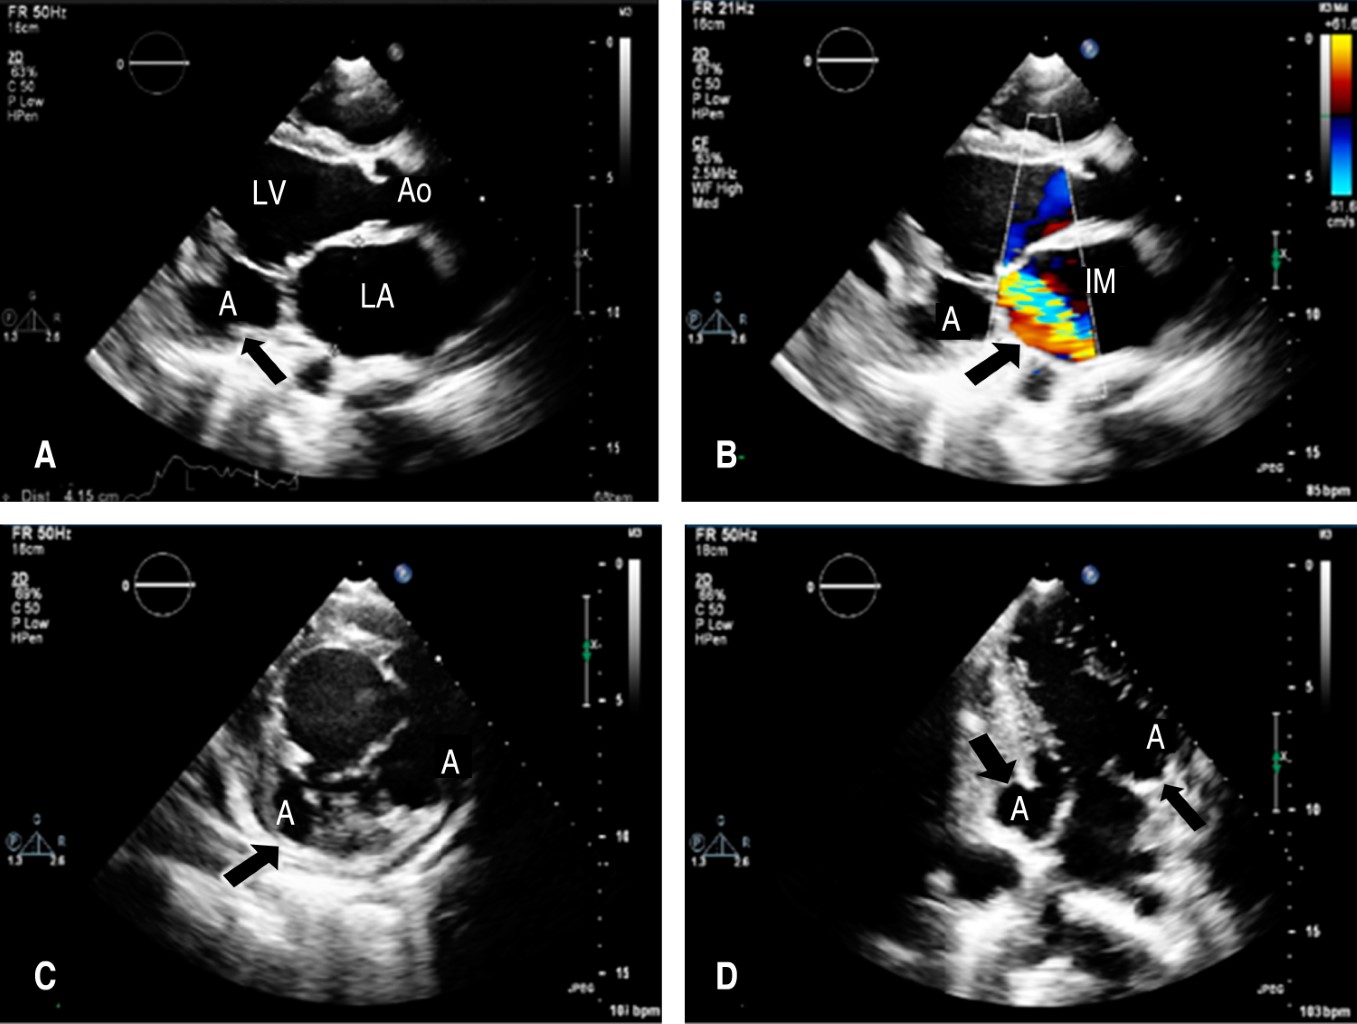

Aneurisma de presentación como causa de insuficiencia de la válvula mitral

Antunes-Vicente MB, Alarcón CH, Ravelo-Dopico R, Lima-Domingos LM, Méndez-Peralta T, Pedro A

Aneurisma ventricular cardiaco, aneurisma subvalvular mitral, insuficiencia valvular, falla cardiaca, cardiopatía congénita.

El aneurisma ventricular subvalvular mitral se considera una rara afección cardiaca con un origen aún no bien definido. Desde su primer informe por Corvisart en 1812, varios informes han coincidido en señalar su mayor incidencia entre los africanos, lo que ha sido escenario de varias discusiones hasta hoy. Existen varias controversias en torno a este tema, el consenso actual es de varios factores interrelacionados como la debilidad del anillo fibroso posterior de la válvula mitral está en la base de su aparición que puede ser de base sostenida, aneurisma congénito, procesos infecciosos, inflamatorios o degenerativos que involucran el endocardio. El diagnóstico de certeza se realiza mediante ecocardiograma y el tratamiento es eminentemente quirúrgico. Se describe el caso de una paciente de 28 años, de nacionalidad angoleña, con aneurisma subvalvular mitral como causa de regurgitación mitral severa e insuficiencia cardiaca, que fue corregida quirúrgicamente con éxito.

Figura 2